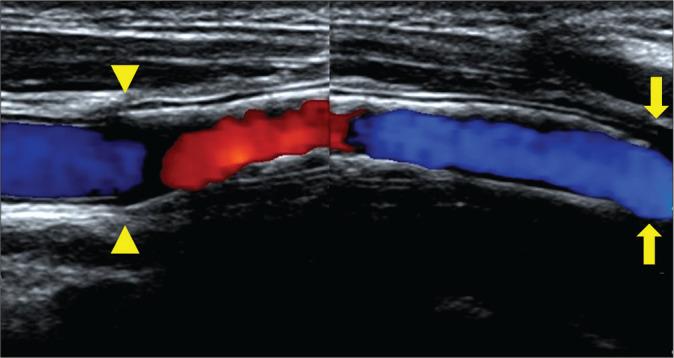

A woman in her 20s experienced injury to the right carotid artery during an operation for removal of a carotid body tumor 6 years before presentation. The right common carotid artery and internal carotid artery were replaced with an artificial vessel graft at that time. Intraluminal stenosis in the graft was not identified 3 years after surgery; however, 4 years after surgery, stenosis was recognized at the non-anastomotic site inside the artificial vessel graft. Subsequently, antiplatelet therapy was initiated. The stenosis was noted to progress gradually in follow-up appointments. Therefore, we decided to intervene because of the patient's young age and the risk of long-term hemodynamic stress. Angiography revealed pseudo-occlusion in the artificial vessel. Percutaneous transluminal angioplasty was performed for stenosis with distal protection; subsequently, CAS was performed. The patient was discharged without neurological deficits 4 days after the operation, and no apparent restenosis was observed as of the 1-year follow-up.